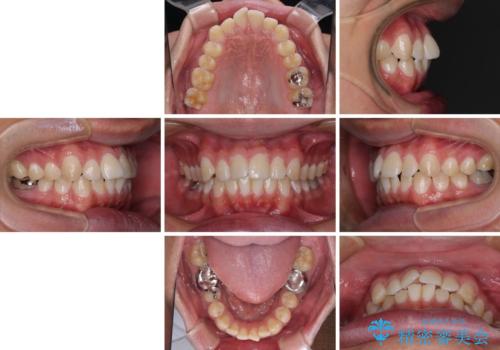

- 前歯のデコボコを気にして来院された患者様です。

ワイヤー装置でもマウスピースでも対応可能でしたが、自己管理の煩わしさを気にされ、ワイヤー装置にて矯正治療を行うこととしました。

矯正治療後は、奥歯の銀歯をセラミッククラウンにて補綴治療を行うこととしました。